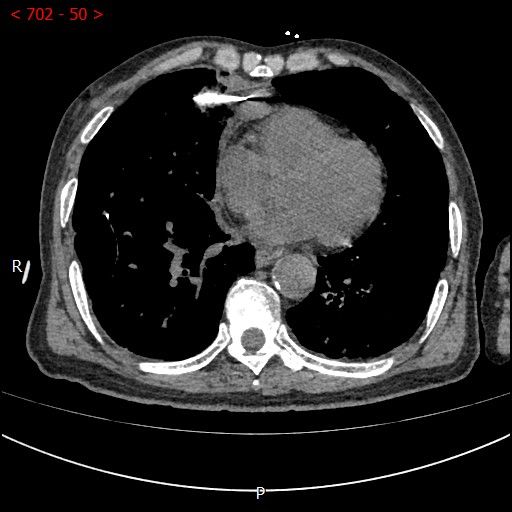

术中影像

男性患者,68岁,检查发现右肺中叶肿块,大小约3.5cm×2.4cm,因患者有慢性支气管炎、肺气肿、肺大泡,基础病较多,无法耐受常规外科手术治疗;经与患者本人及家属多次沟通。血管介入科团队根据患者具体情况决定对该患者施行CT引导下肺肿瘤射频消融术。经全科术前讨论:肿瘤位置毗邻心脏、纵膈、胸膜多处重要器官,手术要求穿刺精准,消融位置精确,尽量避免恶性心率失常,心脏包膜、胸膜、纵膈损伤。经过前期的精心术前准备,2023年7月18日,在血管介入科团队和CT室默契配合下,此次射频消融手术顺利完成。手术全过程仅用时约40分钟,其中消融时间约5分钟。CT观察下见肿瘤形变,周围肺组织呈现“晕”征,提示本次消融范围基本覆盖全肿瘤。术中患者无疼痛并且未产生并发症。本次手术达到杀死肿瘤细胞的同时,最大限度的减少创伤、保留肺组织。